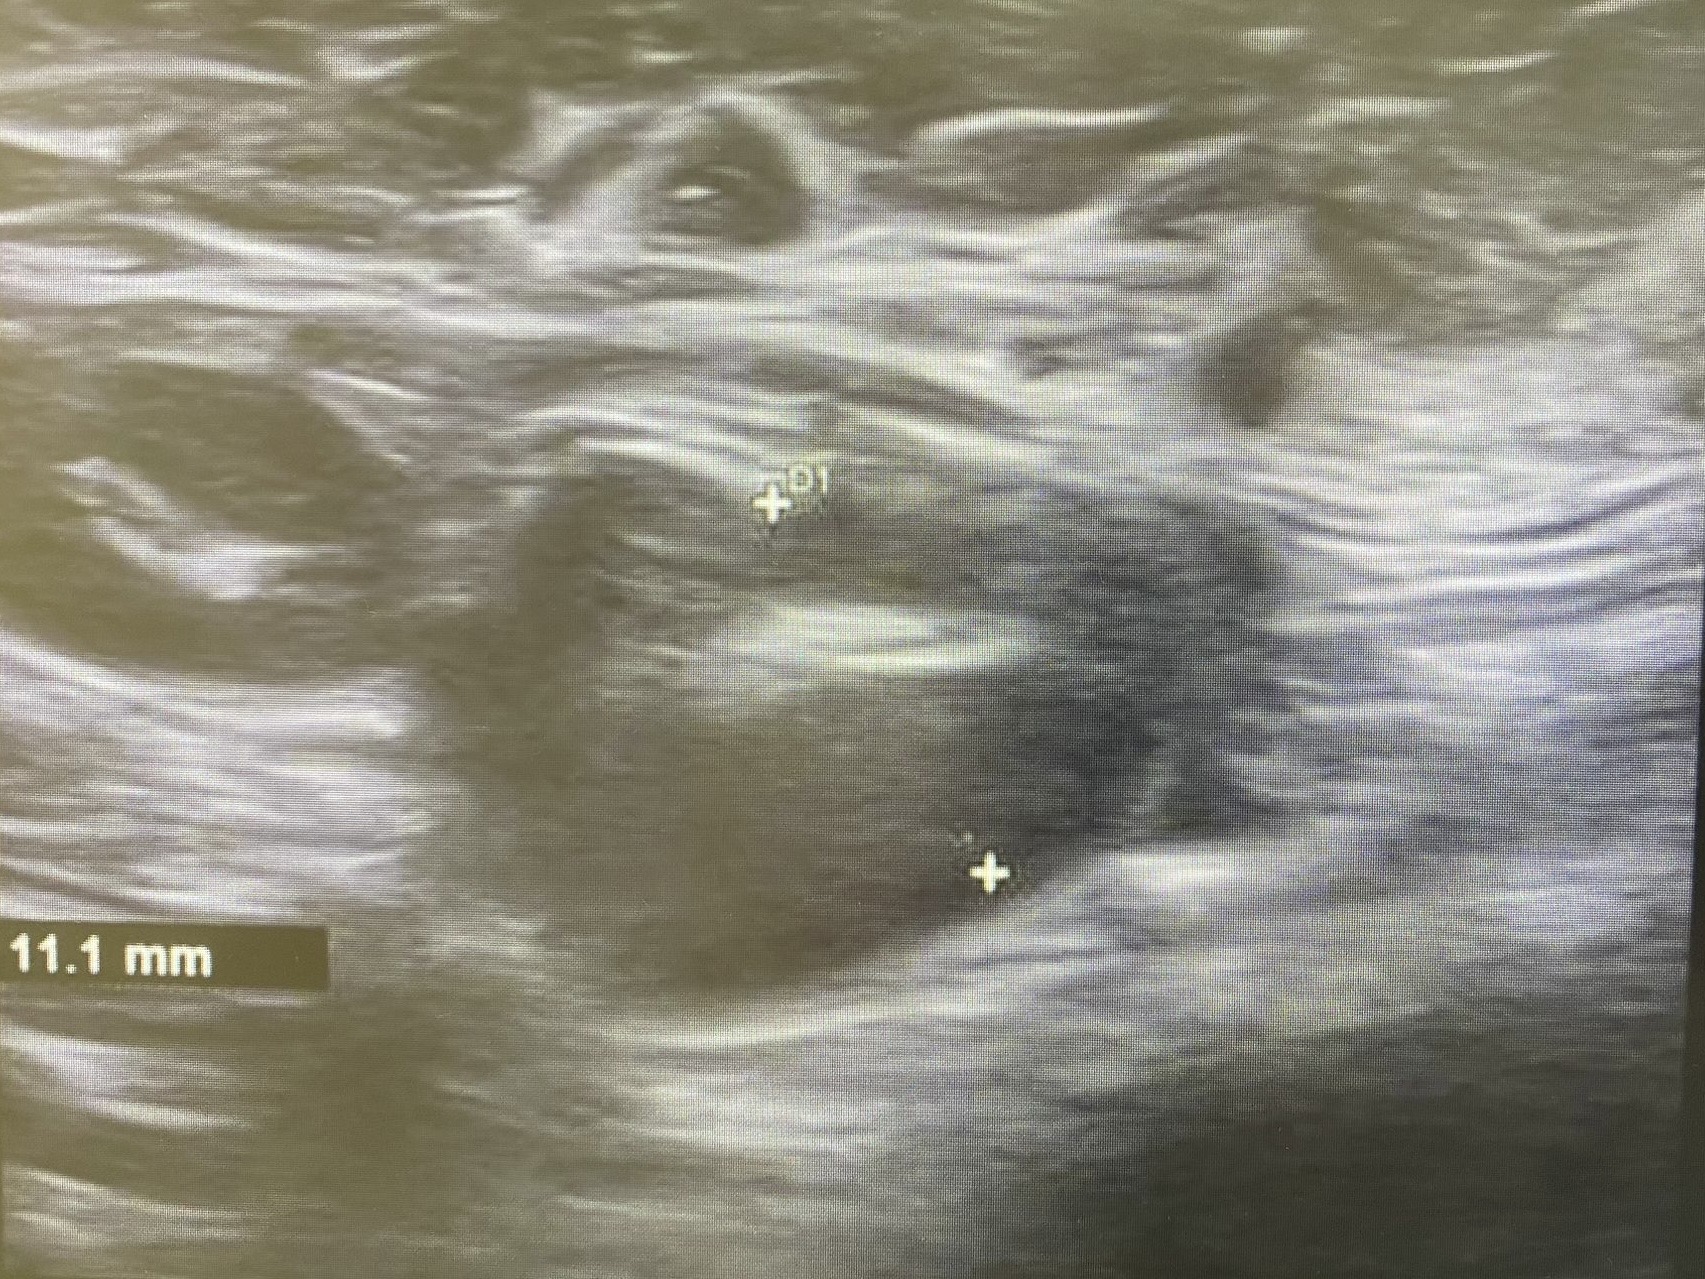

Ecografía: Valoración de adenopatías para acercamiento diagnóstico (típicas/atípicas).

Hallazgos ecográficos

Adenopatías patológicas, algunas redondeadas, con eje anteroposterior > 1 cm, parénquima homogéneo, cortical engrosada aunque con hilio respetado.

Ecografía mamas: quistes y nódulos hipoecogénicos bilaterales.

Ecografía axilar: múltiples adenopatías con eje corto > 2 cm y cortical engrosada.